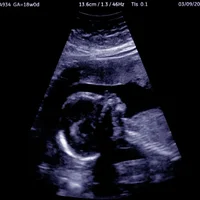

Malformations fœtales et anomalies du développement

Malformations congénitales